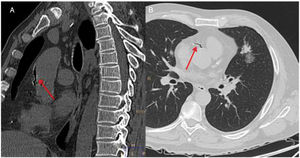

A follow-up chest CT was performed after the CNB, In that examination, a small left pneumothorax and local perinodular hemorrhage were observed, along with a small amount of air in the ascending thoracic aorta and the right coronary artery (Fig. 1). The patient then experienced a sudden decrease in his level of consciousness (Glasgow Coma Scale 5/15), with arterial hypotension (BP 80/40mmHg), bradycardia (HR 35bpm), and marked desaturation (oxygen saturation by pulse oximetry less than 50%), requiring orotracheal intubation and connection to mechanical ventilation. An electrocardiogram was subsequently performed that showed alterations consistent with complete atrioventricular block and acute coronary syndrome, with anterior ST segment elevation. Given these findings, atropine and an infusion of norepinephrine were administered, with subsequent recovery of heart rate and BP. In view of the possibility of a concomitant cerebral embolism, given the neurological symptoms described, we also performed a head CT scan, which showed no acute intracranial alterations, and the patient was admitted to the intensive care unit (ICU) for monitoring and follow-up.